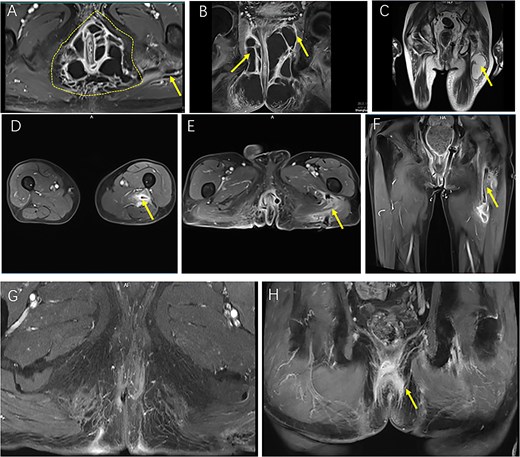

Sequential MRI images illustrating the preoperative extent, postoperative course, and resolution of a complex horseshoe perianal abscess with deep gluteal involvement following surgical drainage. (A, B) Preoperative CE FS-T1-TSE axial (A) and coronal (B) MRI images demonstrate a complex horseshoe-shaped perianal abscess involving both ischiorectal fossae (outlined by a dashed line). The abscess extends superiorly to the apex of the left ischiorectal fossa with associated inflammatory changes involving the left levator ani muscle (arrow). A small secondary gluteal abscess is also noted (arrow). (C) T2WI-FS coronal MRI five days postoperatively demonstrates a deep gluteal abscess (arrow). (D–F) Two-week postoperative CE FS-T1-TSE MRI shows the gluteal region in axial view (D), the perianal region in axial view (E), and the perianal region in coronal view (F), with the left ischiorectal fossa drain accurately positioned at the apex and marked reduction of inflammatory infiltration and abscess cavities. (G, H) Follow-up CE FS-T1-TSE MRI images obtained three months postoperatively in axial (G) and coronal (H) planes show near-complete resolution of inflammation. No residual abscess is observed (arrow).

By postoperative day 5, although the fever had subsided, the patient reported worsening gluteal and thigh pain with impaired mobility and antalgic gait. Ultrasound and pelvic MRI confirmed a deep abscess within the gluteus maximus (Fig. 2C). Multidisciplinary consultation was obtained, and on postoperative day 7, ultrasound-guided catheter drainage under spinal anesthesia evacuated ~200 ml of purulent fluid without complications (Fig. 1C–E).

Follow-up MRI at 2 weeks demonstrated marked resolution, and perianal drains were converted to lose setons (Figs 1F and 2D–F). By postoperative week 3, the gluteal catheter was removed (Fig. 1G). Complete recovery was achieved by 8 weeks (Fig. 1H), and at 3-month MRI and 6-month clinical follow-up, no recurrence was detected (Figs 1I and 2G and H).